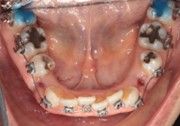

The IOS Mini Cinch Back Plier demonstrated superior control and a significantly reduced risk of bracket debonding and wire deformation compared to the regular Hammerhead plier from a different brand. Wire bends achieved with the IOS Mini Cinch Back Plier maintained integrity even under high-torque activation. The following images illustrate key differences in bend quality, wire distortion, and proximity to the bracket between the IOS Mini Cinch Back Plier and the conventional Hammerhead plier.